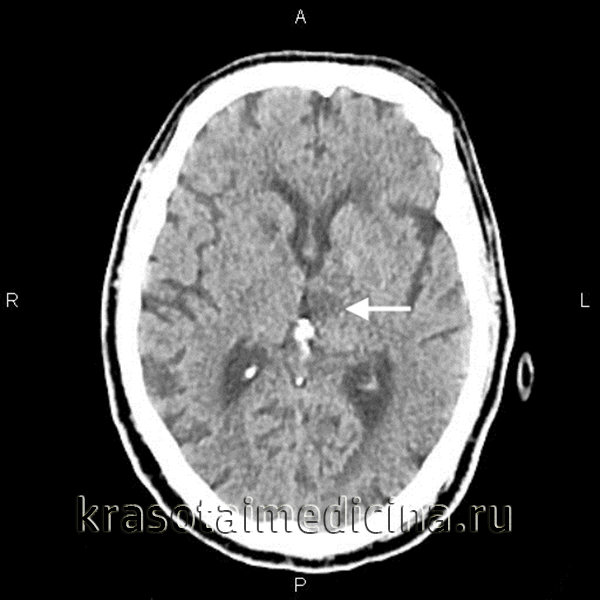

2. КТ первичного артериита ЦНС:

• Бесконтрастная КТ:

о Относительно нечувствительный метод; изменений часто не наблюдается

о Возможно обнаружение вторичных изменений, таких как ишемия или инфаркт:

- Мультифокальные гиподенсные области, особенно типична локализация в структуре базальных ганглиев, субкортикального белого вещества

о Возможна визуализация кровоизлияния (менее типично)